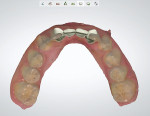

Once it was determined that restorative space was adequate and the proposed tooth proportions were acceptable, the design was finalized. In addition to the standard single lingual retainer wing, a buccal extension was added to the zirconia frameworks (Figure 4), in a "c-wing" design. The frameworks were milled in zirconia and tried in to confirm fit and retention (Figure 5). Following the approved smile design, individual lithium-disilicate veneers(IPS e.max® CAD, Ivoclar Vivadent, ivoclarvivadent.com)were then pressed to fit retainer teeth, adjacent teeth, and prepared pontics on the framework (Figure 6).

After try-in and patient approval, the zirconia frameworks (IPS e.max® ZirCAD, Ivoclar Vivadent) were treated and bonded per manufacturer's instructions and excess cement was cleaned. The veneers were then treated and bonded with a dual-cure resin cement (Variolink® Esthetic, Ivoclar Vivadent) per manufacturer's instructions (Figure 7). At follow-up, the occlusion was verified, and the patient's home care was evaluated.